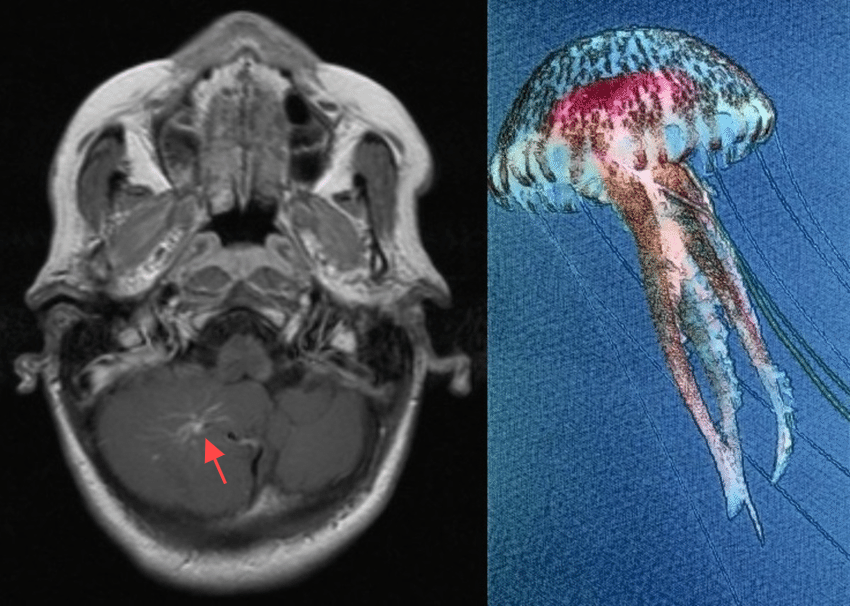

发育性脑静脉异常(DVA):大脑里的“小秘密”

我们前段时间接诊过一位癫痫的青年女患者,在头颅核磁检查时发现右侧额叶发育性静脉异常(DVA),增强核磁明确。它听起来有点吓人,但其实大多数情况下,它并不会给我们带来麻烦。今天,就让我们一起来揭开这个大脑“小秘密”的神秘面纱。 一、DVA是什么? DVA是一种血管结构的异常。正常情况下,大脑里的静脉血管像一条条小河,把血液从大脑的各个角落带回心脏。但在DVA的情况下,这些小河的排列方式有些特别,它们会像放射状一样汇聚到一个扩张的静脉通道中,这个通道就像是一个“收集站”,把血液集中起来再送回心脏。这种结构在影像学检查中看起来像章鱼或水母的触手,所以也被称为“章鱼头征”或“水母头”征。 二、DVA有多常见? DVA其实并不罕见,它在人群中的发病率高达3%左右。也就是说,每100个人中,可能就有3个人有这种病变。不过,大多数人都不会察觉到它的存在,因为它通常没有症状,往往是在做其他检查时偶然发现的。 三、DVA是怎么形成的? 关于DVA的形成,目前还没有完全确定的原因,但科学家们有一些推测。一种观点认为,在胎儿发育过程中,大脑的静脉系统原本应该按照一定的模式发育,但由于某些原因,比如血流动力学的改变,正常的静脉发育受到了阻碍,身体就自动开辟了一条新的“道路”,形成了DVA。另一种观点则认为,可能是胎儿期的静脉血栓导致了正常的引流路径被堵塞,血液不得不寻找新的出路,从而形成了DVA。还有一种说法是,DVA可能是一种静脉解剖的变异,它就像是一种特殊的“排水系统”,承担着特定脑区的静脉引流功能。 四、DVA会带来什么问题?虽然DVA本身是良性的,大多数情况下不会引起症状,但它有时候会和一些其他病变“搭伙”,这就可能带来一些麻烦。比如,大约8%-33%的DVA会和脑海绵状血管瘤“相伴而生”。海绵状血管瘤是一种血管畸形,它的血管壁比较脆弱,容易破裂出血。当DVA和海绵状血管瘤在一起时,出血的风险就会增加。另外,DVA还可能和一些颅面部的静脉畸形、眼眶淋巴管畸形等疾病有关联。不过,这些情况相对较少。 五、DVA需要治疗吗?一般来说,DVA本身不需要治疗。因为它是大脑正常静脉引流的一部分,如果贸然去干预它,比如进行手术或栓塞,可能会导致静脉梗死,给大脑带来更严重的伤害。所以,对于大多数DVA患者来说,保守治疗是最好的选择。但如果DVA和海绵状血管瘤等其他病变一起存在,并且这些病变需要治疗,那么在治疗过程中,医生会特别小心地保护DVA,以确保大脑的静脉引流不受影响。 六、如何发现DVA? DVA通常是在做CT、MRI等影像学检查时偶然发现的。在这些检查中,DVA会呈现出特征性的“章鱼头征”。如果医生怀疑有DVA,可能会进一步做血管造影等检查来确认。不过,对于已经确诊的单纯DVA,一般不需要频繁地做后续检查。 总之,DVA是一种相对常见的脑血管病变,虽然它可能会和一些其他病变相关联,但大多数情况下是良性的。了解了这些知识后,如果你或你的家人偶然在检查中发现了DVA,也不必过于担心。在医生的指导下,进行适当的观察和保守治疗,通常就能很好地管理这种病变。